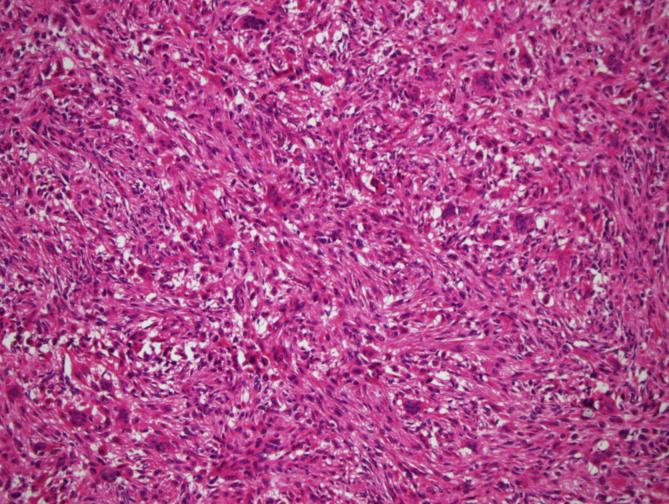

Tumors were localized most frequently at proximal tibia and distal femur, respectively. In 11 cases areas rich in fibrohistiocytic component and in 20 cases aneurysmal bone cyst like component were observed. In 2 cases both components were present. Twenty three cases recurred. In 1 case which was primarily located at calcaneus, tumor metastasized to lung 4 years later during follow-up.

GCT can be confused with other tumor or tumor-like lesions involving giant cells. Secondary changes such as fibrohistiocytic or aneurysmal bone cyst-like components and coagulation necrosis were frequently seen in conventional giant cell tumor of bone. For tumors having prominent fibrohistiocytic and/or aneurysmal bone cyst-like components, in order to detect characteristic areas representing GCT, additional sampling is essential. Although secondary histopathological changes do not appear to affect clinical outcome, these features are important in differential diagnosis. Approximately one fifth of GCT cases show recurrence and sacrum and foot bones were the most frequent sites for recurrence.

肿瘤最常分别位于胫骨近端和股骨远端。在11例中观察到富含纤维组织细胞成分的区域,20例中观察到动脉瘤样骨囊肿样成分。2例中两种成分均存在。23例复发。1例最初位于跟骨,随访4年后肿瘤转移至肺。

骨巨细胞瘤可能与其他涉及巨细胞的肿瘤或肿瘤样病变相混淆。在传统骨巨细胞瘤中,常见纤维组织细胞或动脉瘤样骨囊肿样成分以及凝固性坏死等继发性改变。对于具有显著纤维组织细胞和/或动脉瘤样骨囊肿样成分的肿瘤,为了检测代表骨巨细胞瘤的特征区域,额外取材至关重要。尽管继发性组织病理学改变似乎不影响临床结果,但这些特征在鉴别诊断中很重要。约五分之一的骨巨细胞瘤病例会复发,骶骨和足部骨骼是最常见的复发部位。